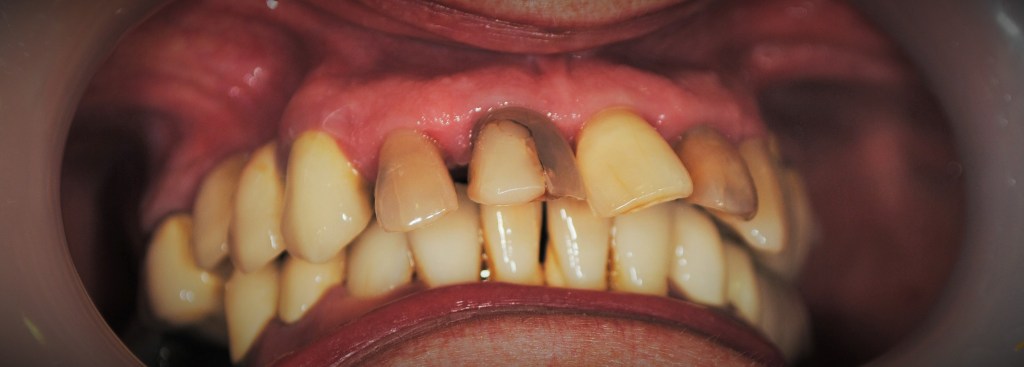

Kozmetikai és funkcionális kezelés: felső torlódott fogak kiegyenesítése, koronák enyhe kifele döntése, mélyharapás korrigálása.

A választott korona típusa: CAD/CAM (komputer vezérelt tervezés/megmunkálás) technológiával készült cirkónium (fémmentes) szóló koronák.

A választott fogszín: A2

A protetikai munka elkészülésének ideje: 5 munkanap.